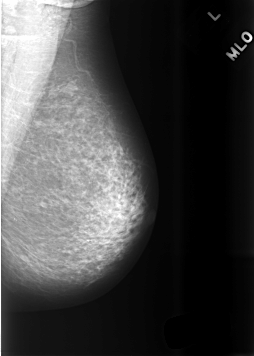

ics_version 1.0 filename C-0475-1 DATE_OF_STUDY 2 10 1995 PATIENT_AGE 66 FILM FILM_TYPE REGULAR DENSITY 2 DATE_DIGITIZED 10 2 1999 DIGITIZER LUMISYS LASER SEQUENCE LEFT_CC LINES 5616 PIXELS_PER_LINE 3944 BITS_PER_PIXEL 12 RESOLUTION 50 NON_OVERLAY LEFT_MLO LINES 5696 PIXELS_PER_LINE 4064 BITS_PER_PIXEL 12 RESOLUTION 50 NON_OVERLAY RIGHT_CC LINES 5728 PIXELS_PER_LINE 3936 BITS_PER_PIXEL 12 RESOLUTION 50 OVERLAY RIGHT_MLO LINES 5720 PIXELS_PER_LINE 4040 BITS_PER_PIXEL 12 RESOLUTION 50 OVERLAY |